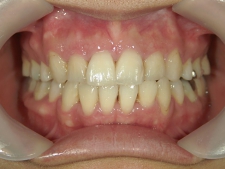

矯正歯科 治療後矯正歯科 全顎ワイヤー矯正 治療後矯正歯科(全顎ワイヤー矯正)治療後

矯正歯科 治療後

no.31_1962_治療後_右.JPGno.31_1962_治療後_正面.JPGno.31_1962_治療後_左.JPG